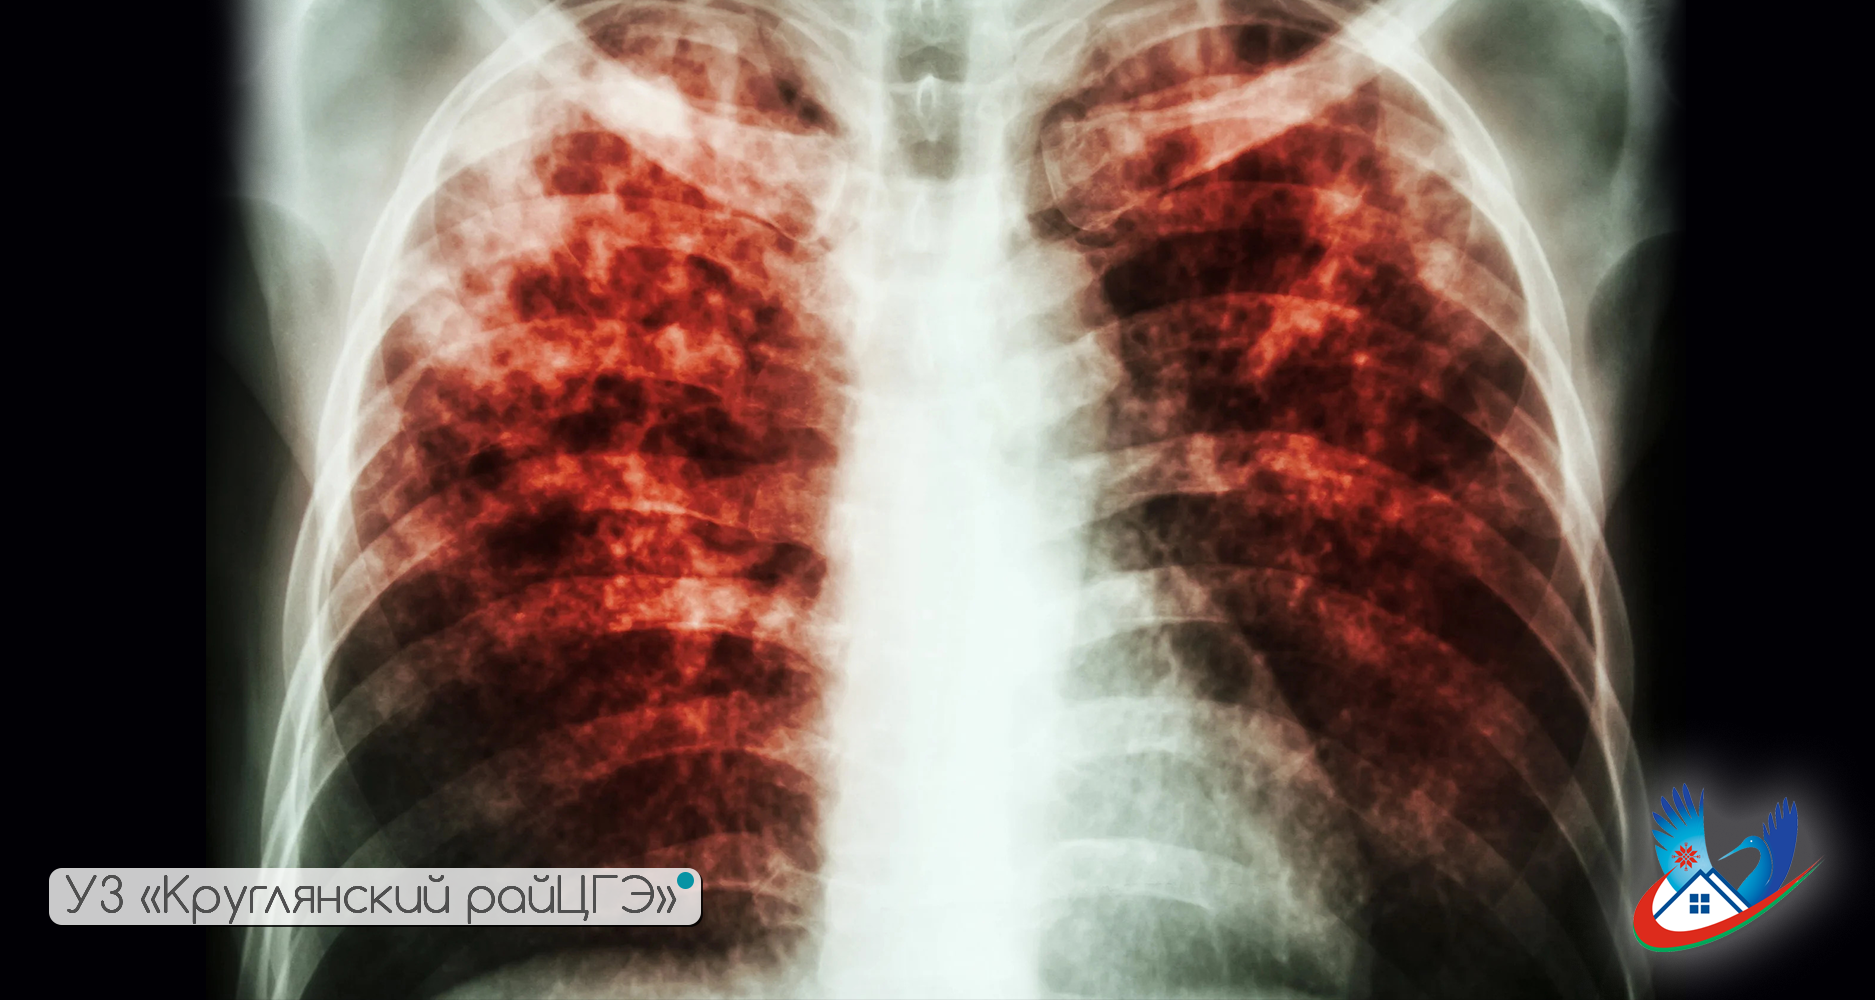

ПРЕСС-РЕЛИЗ 24 марта – Всемирный день борьбы с туберкулезом.

Туберкулез – это инфекционное заболевание, вызываемое микобактерией туберкулеза (далее – МБТ) и характеризующееся различной (преимущественно легочной) локализацией, разнообразием клинических проявлений и интоксикацией организма.

Единственным способом выявить болезнь на ранних этапах развития являются флюорографическое и бактериологическое исследования. Для профилактических осмотров населения организации здравоохранения Могилевской области оснащены рентгеновскими аппаратами нового типа («Пульмоэкспресс») с низкой лучевой нагрузкой. Бактериологические лаборатории укомплектованы современным оборудованием и расходными материалами, включая автоматизированные системы для ускоренной диагностики возбудителя туберкулеза, которые позволяют, по сравнению с обычным исследованием, сократить время получения результатов. Используются экспресс-методы молекулярно-генетической диагностики множественной лекарственной устойчивости микобактерий туберкулеза. Проблема диагностики заболевания важна, так как своевременный диагноз туберкулеза необходим для своевременного лечения пациента, поскольку туберкулез, как правило, излечим.